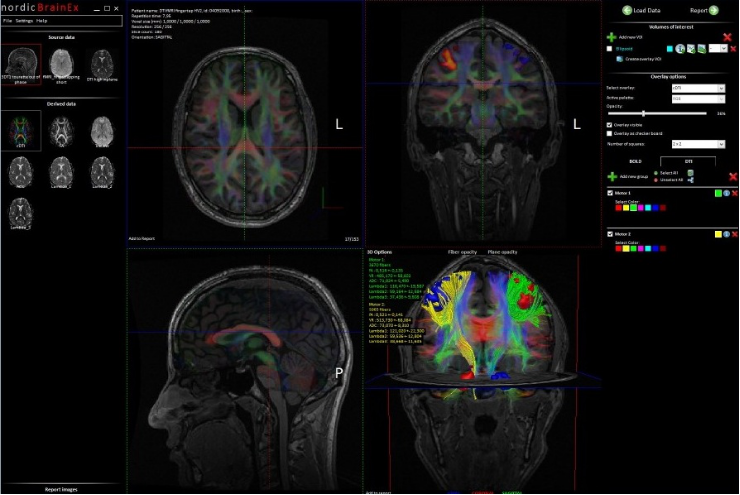

NordicBrainEx是專爲臨床設計的fMRI後處理軟件。簡易而功能強大的界面提高瞭(le)用戶的工作效率。先進的感興趣體積工具、BOLD激活區域的2D/3D可視化、DTI纖維追蹤成像和灌注MRI圖讓臨床醫生可對病竈周圍區域的大腦組織進行廣泛且深入的評估。(對於(yú)腫瘤的分類,分級,術中導航以及治療後的跟蹤監測有重要作用)

1.BOLD fMRI、DTI和DSC灌注圖像重疊(dié)在同一視(shì)圖中,擁有清晰的視(shì)圖和分析方案。

3.快速生成DTI處(chù)理後(hòu)圖像(cDTI、FA、Trace、ADC、Lambda圖)和快速纖維追蹤算法。

DTI 纖維束追蹤模塊